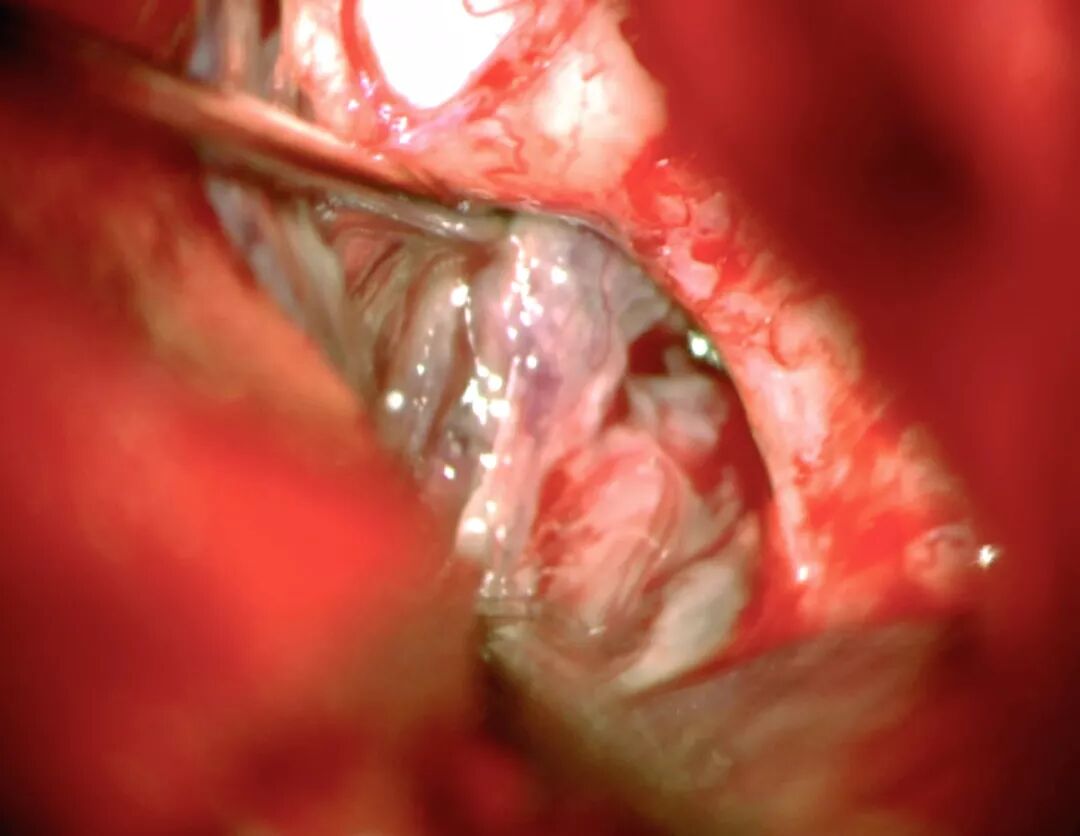

图5:经左侧眶颧开颅显露终板(术前相关图像见图1),浅灰色的肿瘤致终板扩大。已标记出前交通动脉复合体,要避免过度牵拉血管结构。读者可体会手术通道的狭窄。

图6:动态牵拉可精准扩大显微器械操作的手术空间。将肿瘤减容后从术腔取出(参见上图5)。经终板入路存在很多手术盲点,这些盲点包括三脑室后方、上方以及同侧下丘脑壁。因此,过度牵拉不可避免,这就会损伤穹隆柱、视上核、终板血管器、灰结节和穿支血管。